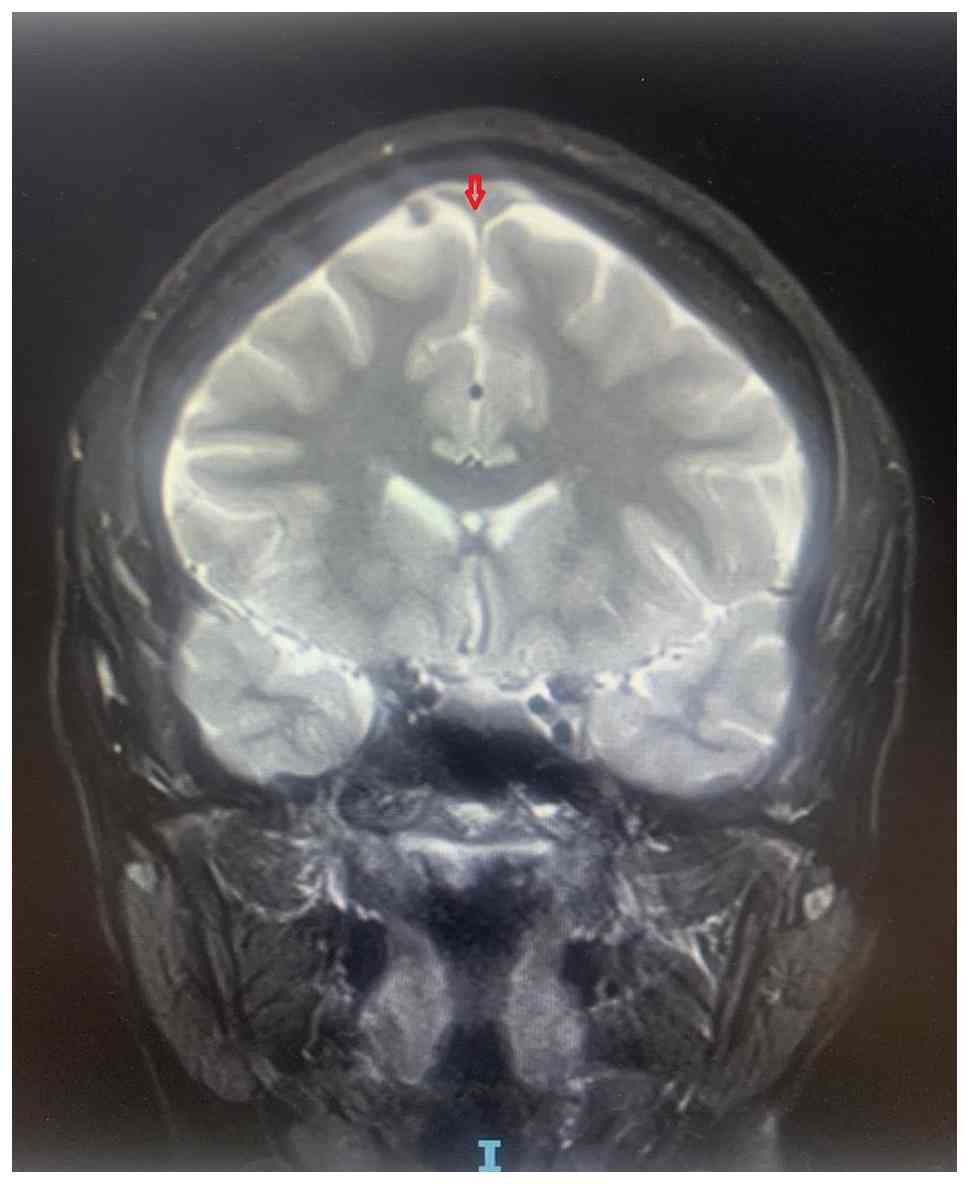

MRI T2-weighted coronal section. The

arrow shows loss of flow void in the superior sagittal sinus. Image

was obtained in June 2023.

Figure 3

MRI T2-weighted coronal section. The arrow shows loss of flow void in the superior sagittal sinus. Image was obtained in June 2023.